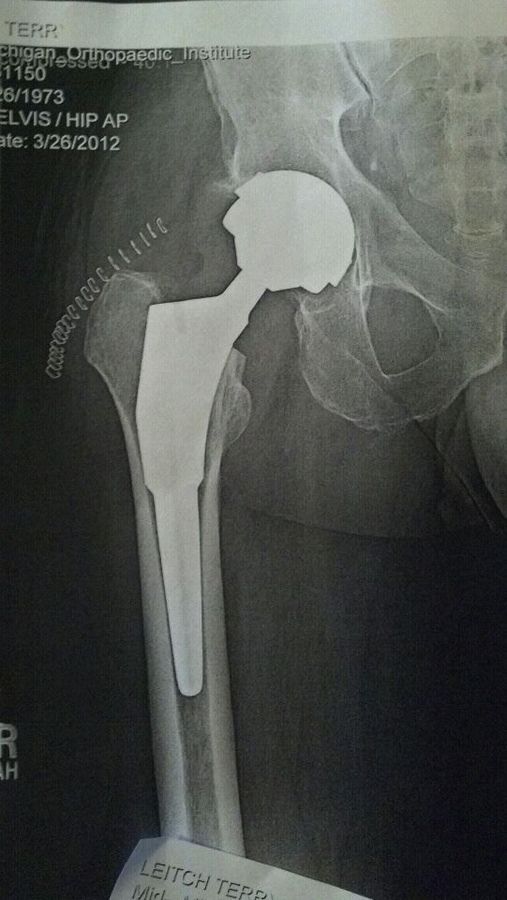

Good thoughts welcome....DH is going in for his hip replacement this afternoon. He's only 38, but has severe degeneration of the joint - the xrays are pretty ugly, and the doctor was surprised he can walk, let alone climb trees every day (he's a line clearance tree trimmer). Luckily, it's only his one hip, the other is in good shape. He'll be off work for up to 3 months (due to his work, he can't go back until he's 100% healed, no "easy" jobs for him to do, it's all go the day he goes back). He's hoping he can be ready to go in two months.

This will be his first surgery under anesthetic, and his first hospital stay. He's pretty positive about it. He'll be getting a metal on metal implant instead of the ceramic or plastic, doctor thinks the metal on metal will be best due to his young age and his line of work. Doc is confident he will be able to return to his job and do it for a long time (until he retires, which is good as he's going to be on a pension, and doesn't have a 401k).